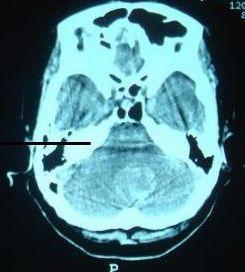

小脑出血吐是怎么回事?

相信小脑出血这个疾病广大的患者们并不陌生,因为它在临床上的发病率是非常高的。而且在临床上小脑出血与高血压病有着直接的关系,并且绝大部分的小脑出血患者都是由高血压病引起的,因此广大的高血压病患者们一定要引起重视。那么脑出血吐是怎么回事下面将为大家详细的进行介绍。

第一:在临床上绝大部分的小脑出血病患者都会出现眩晕以及呕吐,甚至是头痛的现象。严重的患者甚至是呕吐非常频繁,这主要是因为大量的颅内出血,导致了患者们出现了颅内高压的现象所引起的。

第二:在这个时候,患者们一定要到正规的医疗机构进行检查,并且配合医生治疗。而且如果超过48个小时,没有得到良好的治疗的话,是会引起休克的。严重的病患者甚至是会引起脑疝。